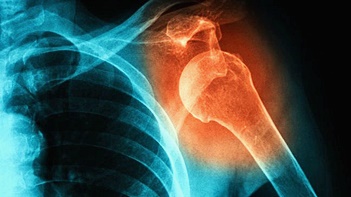

1. 통증

어깨 탈구가 발생하면 먼저 심한 통증이 동반됩니다. 하지만 탈구 증상이 반복적으로 발생하다 보면 통증이 줄어들게 되는데요. 탈구된 방향에 따라 특정하게 고정되어 움직일 수 없게 됩니다.

2. 모양 변형

어깨 탈구가 발생하면 정상적으로 보이지 않고 어깨의 삼각근 부위가 변형되는 모습이 관찰되기도 합니다. 탈구 시 신경 손상이 동반되는 경우 감각이상이나 마비 장애, 색깔 변화, 멍 등의 다른 변화가 나타날 수 있습니다.

3. 불안감

방향에 따라 공 던지는 자세를 취했을 때 팔이 빠지는 느낌이 들기도 하는데요. 무거운 물건을 들면 아래로 팔이 쳐지면서 통증이나 불안감을 느낄 수 있습니다. 증상이 잦은 경우 증상에 대한 두려움으로 관절운동을 피하게 될 수 있습니다.